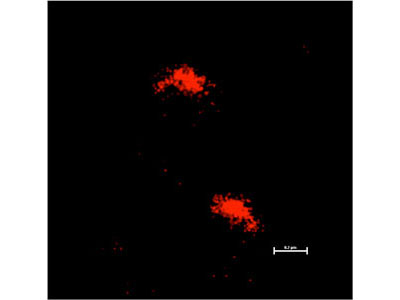

Throughout history, tuberculosis (TB) has taken a remarkable toll on human health. Even today, more than 50 years after the advent of antibiotic therapy, this infection kills millions every year. The resilience of this disease in the face of modern treatment is largely a result of the unusual biology of the causative agent, Mycobacterium tuberculosis. Our lab is focused on understanding the physiology of the mycobacterial cell, the interactions between host and pathogen, and how these fundamental biological processes influence pathogenesis and antibiotic efficacy.